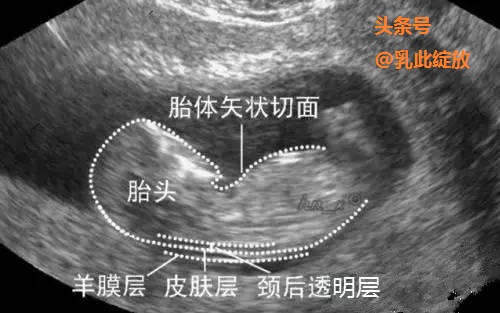

胎儿颈项透明层( nuchal translucency thickness,简称NT): 指胎儿颈椎水平矢状切面皮肤到皮下软组织之间的最大厚度,反映在彩超的声像图上即为胎儿颈后皮下组织内无回声带。

NT是怎么形成的呢:胚胎在淋巴系统健全之前, 由少部分淋巴液积聚在淋巴囊或淋巴管而形成 。是所有的正常胎儿都存在,这个无回声带代表胎儿生理性新陈代谢所产生的液体的积存,是对胎儿脑部一过性过度灌注的保护性表现。在孕 14 周左右, 胎儿的淋巴系统发育完善后, 此处所积聚的淋巴液,则汇入颈内静脉,NT 消失。